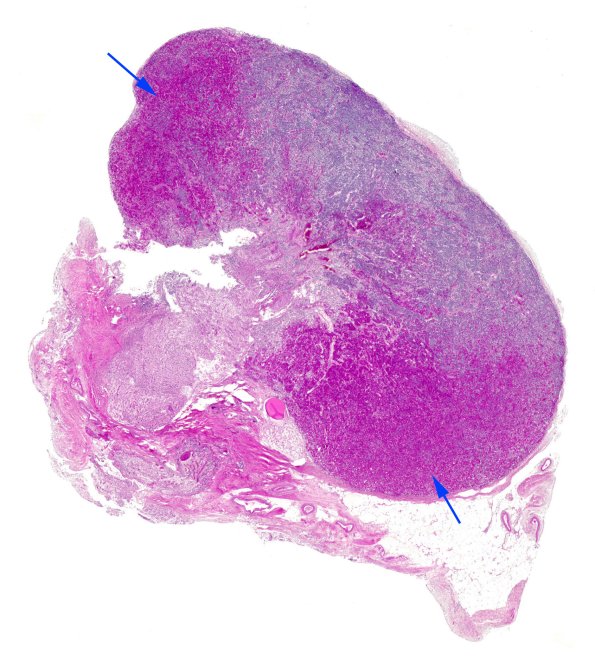

1D1,2 The cells in the pituitary are not homogenously distributed. The arrows in this case identify the “acidophil wings” whose acidophil cells are illustrated in 1D2. (H&E)